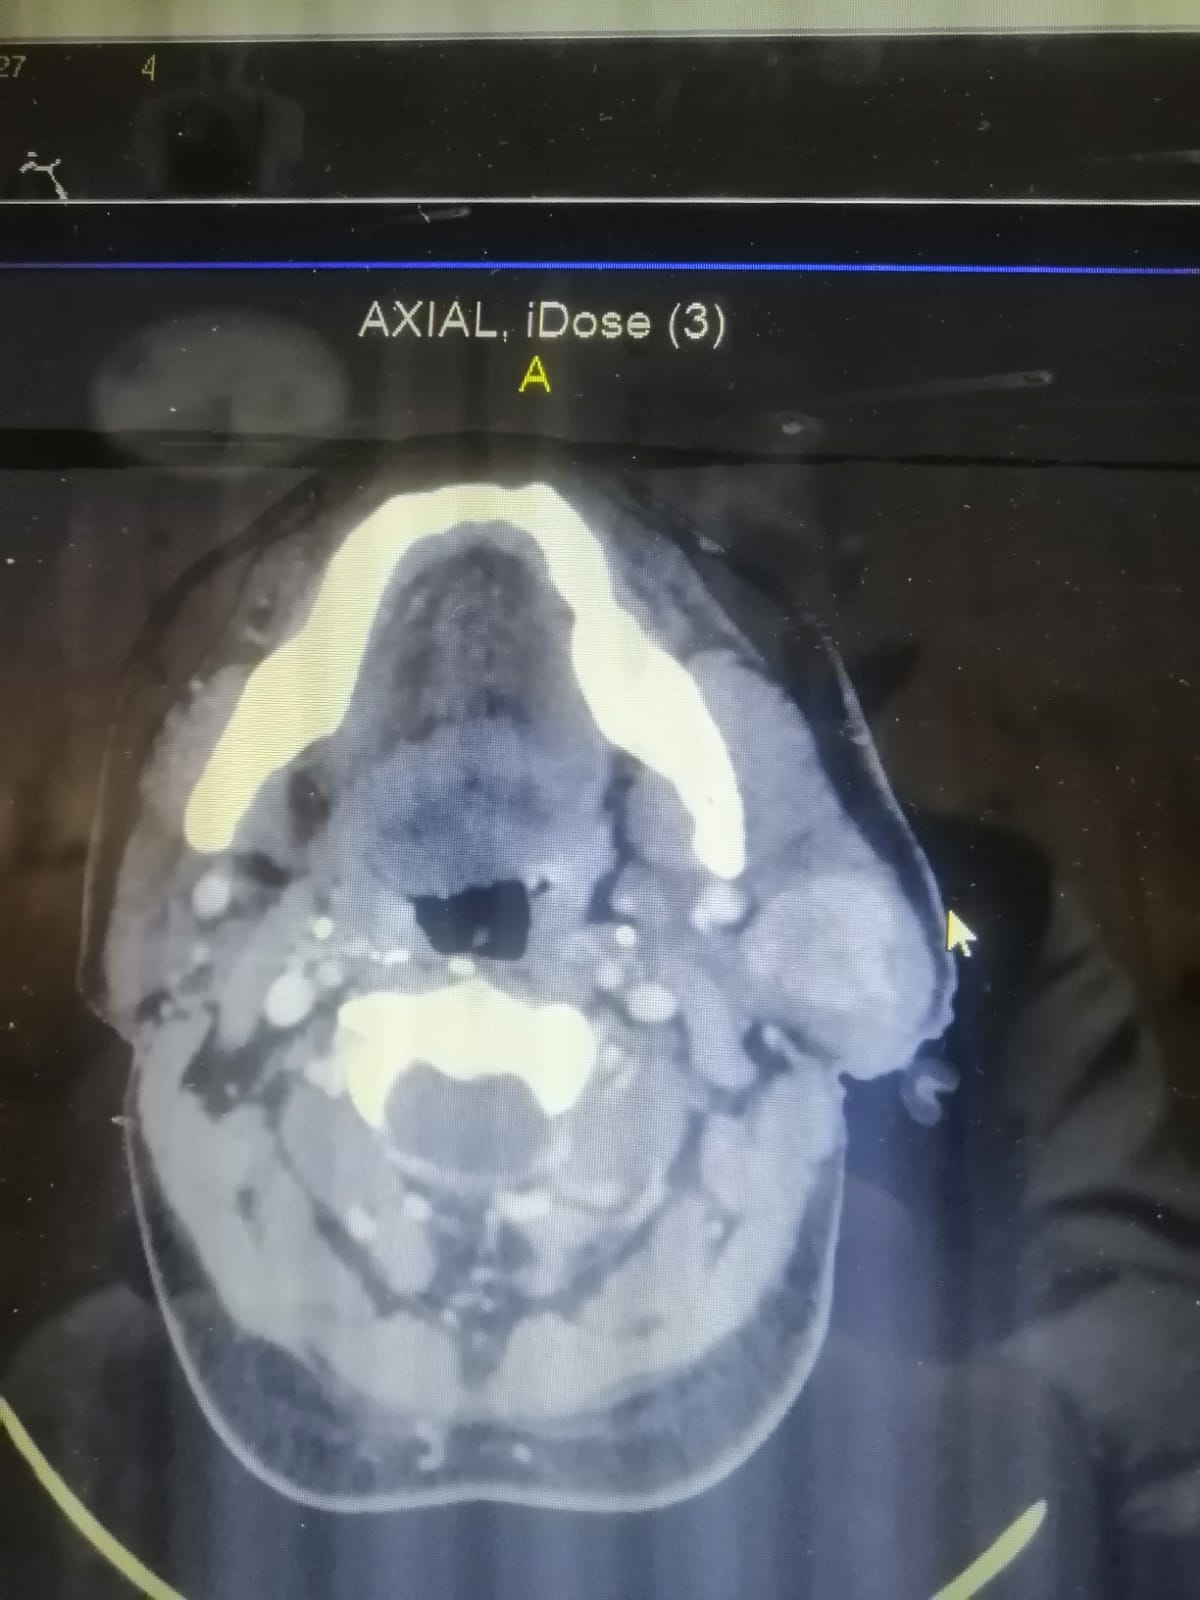

وبين أخصائي جراحة الوجه والفكين بأن المريض الذي يبلغ من العمر (٥٠) عام كان يعاني من انتفاخ وتورم بمنطقة الوجه والرقبة، وبعد الفحص السريري والإشعاعي تبين وجود ورم ليمفي غير سرطاني بالغدة النكافية،